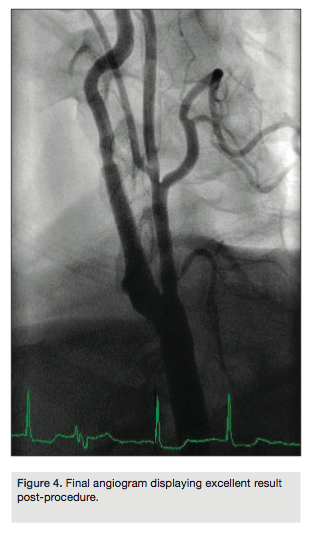

arch aortogram revealed a Type I aortic arch with no significant atheroma (Figure 1). A Simmons 2 catheter (AngioDynamics) was used to selectively engage the right common carotid artery by looping the catheter in the right coronary cusp. A stiff-angled Glidewire (Terumo) was then used as an anchor in the right external carotid artery (Figure 2A) and a Pinnacle Destination sheath (Terumo) advanced into the right common carotid artery (Figure 2B). Selective angiogram confirmed an 80% stenosis of the right internal carotid artery (Figure 3). An Emboshield distal embolic protection device (Abbott Vascular) was deployed in a straight segment in the distal right internal carotid artery. After pre-dilation with a Viatrac 4.0 x 20 mm